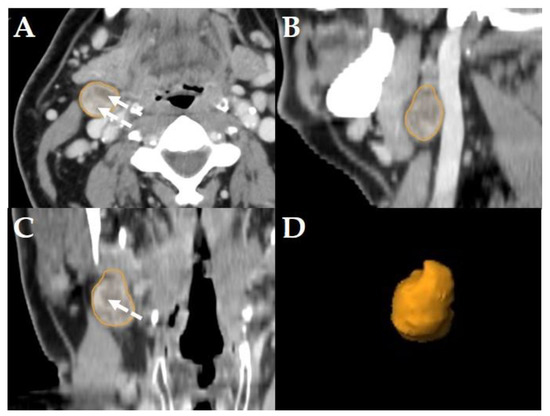

All diagnostic-, planning- and restaging-CTs were imported to the segmentation software (Elements, BrainLab, Munich, Germany). For each patient the three largest LNs were manually segmented in all data sets slice-by-slice in the axial plane using the “paint on slices” tool provided by the software. All segmented LNs were examined by two experienced, board certified head and neck radiologists with more than 15 years of clinical experience in head and neck CT reporting. The segmented LNs were classified as “pathologic” (Figure 2), “pathologic with ECS” (Figure 3) or “non-pathologic” (Figure 4), complying with current CT reading criteria for LN-malignancy [5,6,7].

Figure 3. Example of a LN classified as “pathologic with ECS” in a Staging-CT of a 53-year-old, male HNSCC-patient of the oral cavity staged cT2 cN3b cM0. Manual segmentation in the axial plane (A); sagittal (B), coronal (C) reformatted views and three-dimensional rendering (D) of the LN are provided by the software. Solid arrows show soft tissue infiltration and an irregular LN capsule. Dashed arrows show central necrosis.

LNs were classified “pathologic with ECS” if in staging-, planning- or restaging-CTs, in addition to the criteria mentioned above [5,6], apparent fat/soft-tissue infiltration, infiltration of the sternocleidomastoid muscle, the internal jugular vein, or the carotid artery was observed [7]. Consequently, all LNs classified as “pathologic with ECS” were considered “pathologic”, too, but not all “pathologic” LNs were classified “pathologic with ECS” (Figure 3).

Consequently, the classification of the segmented LNs in “pathologic” (Figure 2), “pathologic with ECS” (Figure 3) and “non-pathologic” (Figure 4) by the two experienced head-and-neck-radiologists based on established criteria [5,6,7] was defined as reference.